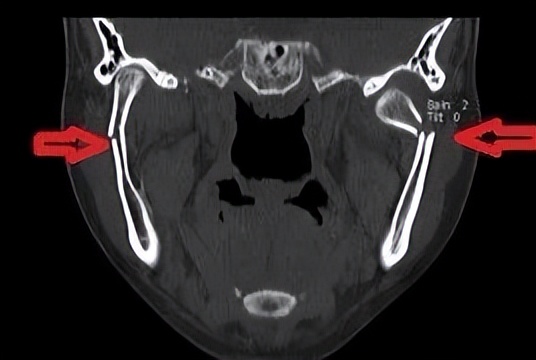

老百姓口中的“下巴”,指的是面部下颌骨区域,医学专业上特指下颌骨前部中份的颏部,俗语也叫“下巴颏子”。颏部因位置突出靠前,受伤瞬间人体反应等因素,该部位容易造成直接损伤,形成软组织裂伤及下颌骨中间部分骨折。然而,由于下颌骨呈马蹄形结构,两侧向上借助升支形成的髁突与颅底结构形成颞下颌关节,如果颏部的直接外力过大,力量沿升支传导向上,就可能造成下颌骨髁突骨折。

髁突骨折较一般下颌骨骨折复杂。首先,髁突参与形成颞下颌关节,该关节是人体最灵活功能最复杂的关节之一,一旦遭受损伤,可能出现咬合紊乱、张口受限、关节强直、关节炎等;由于髁突为生长发育中心,未成年人还可能影响颌面部的发育。其次,髁突骨折分类及相应治疗原则多样,根据骨折高中低位,髁突骨折可简易分为髁头、髁颈、髁基骨折,每种分类又根据移位等情况分为不同亚型,不同分类亚型需正确选择手术适应症,才能达到最佳治疗效果。第三,髁突手术涉及支配面部表情肌的运动神经-面神经,分泌唾液的大腺体-腮腺等重要解剖结构,需熟练掌握手术技巧,以避免面瘫等影响患者美观的并发症。

淄博市中心医院口腔颌面外科团队在下颌骨髁突骨折方面积累了较为丰富的治疗经验,近年来不断更新吸收先进治疗理念。近期,团队对多位合并髁突骨折的下颌骨骨折患者,按照标准治疗理念,或行手术治疗,或保守康复治疗,均取得了良好的效果。此外,为解决切口瘢痕影响美观的问题,团队医生积极开展了发际内结合耳屏后缘、耳后切口等美容切口设计,使手术切口更为隐蔽不可见,满足了年轻患者的美观需要。

最后,在此提醒广大市民朋友,如遇面部外伤,出现咬合错乱,张口受限等症状,切不可掉以轻心,只关注局部损伤。应当及时专科就诊,排除髁突骨折在内的颌面部骨折,以免延误治疗。